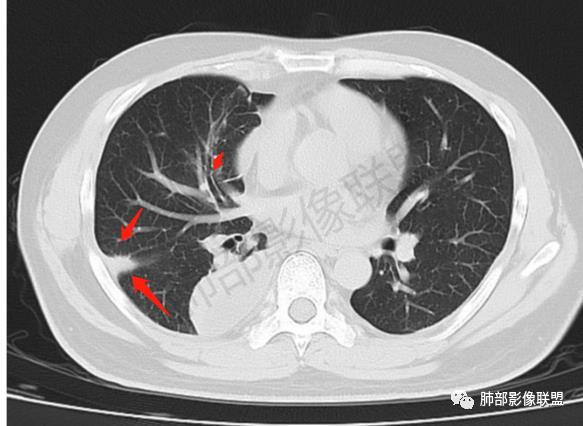

尘缘: @赵永兵 内蒙巴市临河妇幼影像科 左上肺也是胸膜下(胸膜顶下)的SPE。

这个图就是理由

尘缘:

@赵永兵 内蒙巴市临河妇幼影像科 支气管是从旁边经过,所以不是空洞,是胸膜下的脓毒栓。如果是结核空洞,应该与支气管相通(因为结核没有血播感染表现的时候,来源是气道,空洞应该与支气管相通),所以支气管从旁边经过,这病灶又在胸膜下,周围也没有干酪坏死。当然是SPE了。

空洞内壁光滑,偏心厚壁空洞,张力高